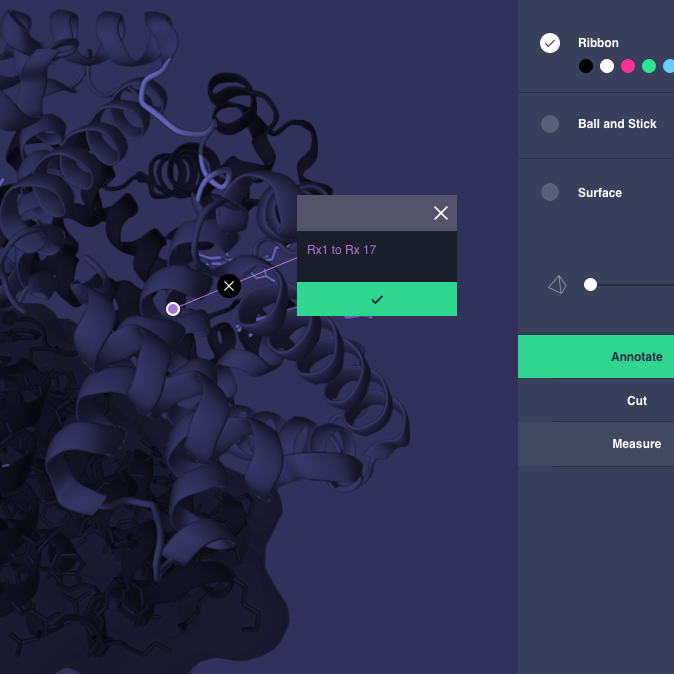

Application

Application